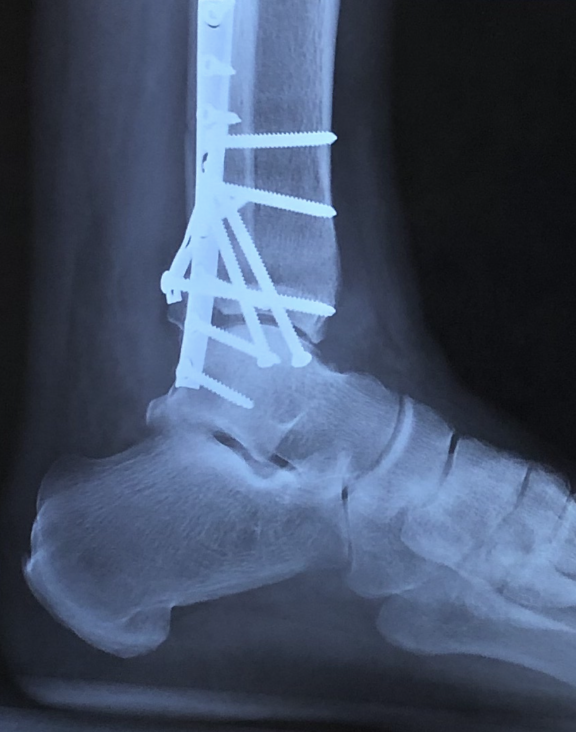

After sustaining a trimalleolar fracture of my left ankle on July 15,2020, Dr. David S. Levine came highly recommended. After my first appointment, he exceeded all trustworthy expectations. Dr. Levine and his (PA) Lauren Buchwald took the time to answer all my questions.